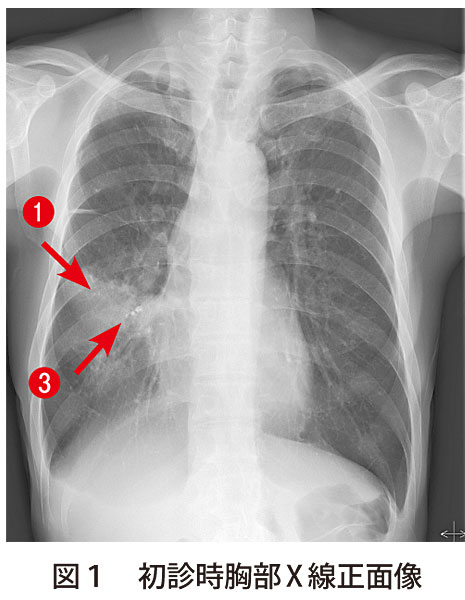

解答 解説 咳嗽 胸痛を主訴に来院した20歳代男性 実践 画像診断q A 羊土社 レジデントノート 羊土社